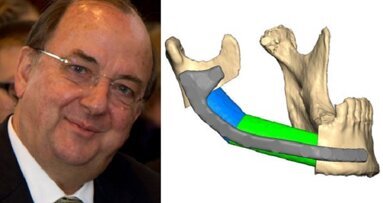

- le lacune ossee sono state trattate mediante cranioplastica; in un caso si procedeva inoltre a rimodellamento fronto-orbitario. Le cranioplastiche sono state effettuate con diversi materiali: osso autologo, metilmetacrilato, matrice ossea demineralizzata (Fig. 1) e cemento;

- i dislocamenti delle “springs” (Fig. 2) e del “Blue Device” (Fig. 3) sono stati affrontati mediante il loro riposizionamento. Nel caso del Blue Device si associava inoltre una frattura con necrosi cutanea; si è dunque proceduto anche a revisione di ferita e riduzione della frattura;